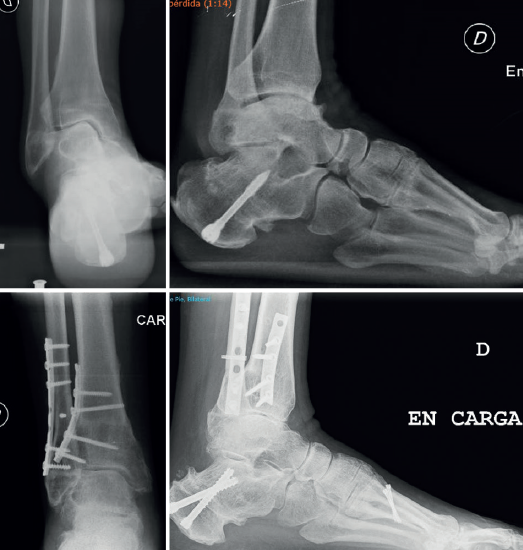

mact.1501.fs2301010-figura5.png

Figura 5. Paciente de 48 años con varo tibiotalocalcáneo intervenido previamente de osteotomía de Dwyer. Osteotomía de sustracción tibial lateral y acortamiento de peroné en Z. Queilectomía talar, ligamentoplastia lateral y transferencia del TTP. Nueva osteotomía de traslación lateral combinada con Zadek y osteotomía de elevación de M1.

En caso de CORA eminentemente intraarticular por erosión medial de la superficie articular tibial medial, nuestra preferencia es la plafón-plastia (Figura 4)(18). Para rellenar la cuña de apertura, preferimos el autoinjerto tricortical de cresta ilíaca y relleno con chips de aloinjerto esponjoso, aunque otros autores emplean placas con escalón metálico y relleno con sustitutivos óseos o aloinjerto tricortical(18). - Osteotomía de cierre lateral: se realiza una incisión de 10 cm sobre la cara lateral preservando el nervio peroneo superficial. Se planifica una osteotomía en Z de 3-4 cm comenzando en la zona más proximal de la sindesmosis anterior. Se colocan 2 agujas de Kirschner de forma oblicua y convergentes desde la zona más proximal de las sindesmosis dirigidas a la antigua placa de crecimiento fisario en la zona medial. Se puede colocar otra aguja de freno para no romper la cortical medial. Si existe fractura de la cortical medial, es recomendable poner 2 placas, una medial y otra lateral (Figura 5).